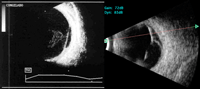

Luxación de cristalino

La luxación de cristalino aparece como complicación en traumatismos oculares o cirugías complicadas, y con frecuencia se acompaña de hemorragia vítrea.

En modo B se aprecia una estructura de superficie regular, con alta reflectancia en su margen anterior y sombra acústica posterior (

Figura 8). Es habitual la presencia de membranas vítreas o de bridas que se insertan en la lente.

Figura 8. Cristalino en el polo posterior. Cara anterior lisa y de alta reflectancia, con importante sombra acústica por su alta densidad.